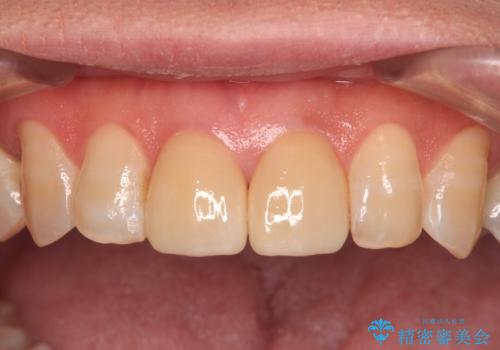

仮歯に置き換えた後にオールセラミッククラウンにて補綴治療を行うこととしました。